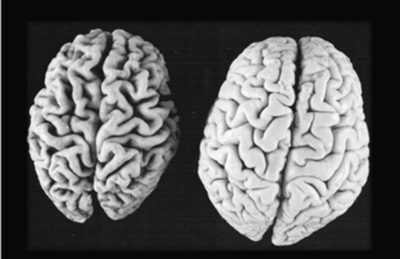

(Alzheimer Immagine Credit Public Domain).